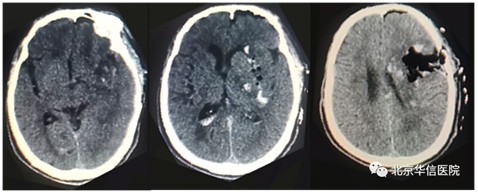

脑出血患者术后2小时头颅CT

患者入院时处于昏迷状态,危在旦夕,情况紧急。经快速周密的术前准备和评估,在麻醉科、手术室的密切配合下,由应建有和焦庆贵主治医师为患者精准实施神经内镜下基底节区脑内血肿清除手术。术中仅在患者头部做一约4cm长的小切口,操作范围为稍大于一元硬币的微骨孔,术中应用气动支持臂辅助,在神经内镜“慧眼”的指引下,电凝出血点,紧张有序地探查血肿并予以清除,术后2小时复查头部CT显示血肿清除干净,手术起到立竿见影的效果。